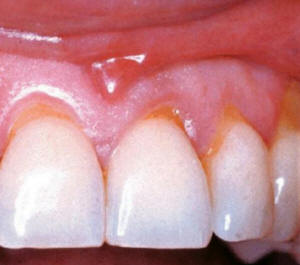

- Antes que nada es preciso registrar con fotografías la

tinción presente en la boca del paciente. Las fotografías son

valiosas como recordatorio de su estado bucal, antes de iniciar

el tratamiento; dado que el paciente suele olvidarse el aspecto

que tenían dientes.

- Explorar la encía:

Gingivitis o enfermedad periodontal leve, moderada y severa contraindica

el tratamiento. Dado que el sangrado y la exposición de la

dentina y cemento malogran los tratamientos blanqueadores. Las

encías retraídas dejan espacios interdentales oscuros, el

cemento dental decolorado no se blanquea. A veces junto con el

tratamiento blanqueador es necesario

confeccionar carillas para eliminar los defectos de color y

forma.